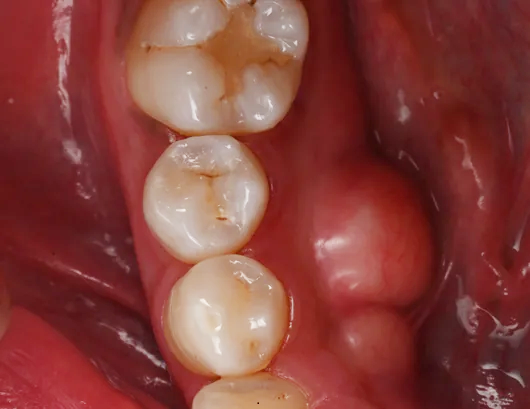

術前

| 治療説明 | 虫歯が発生したため、ダイレクトボンディングを行いました。ラバーダムを装着し、う蝕を除去してレジンを充填し、見た目と機能を回復しました。 |